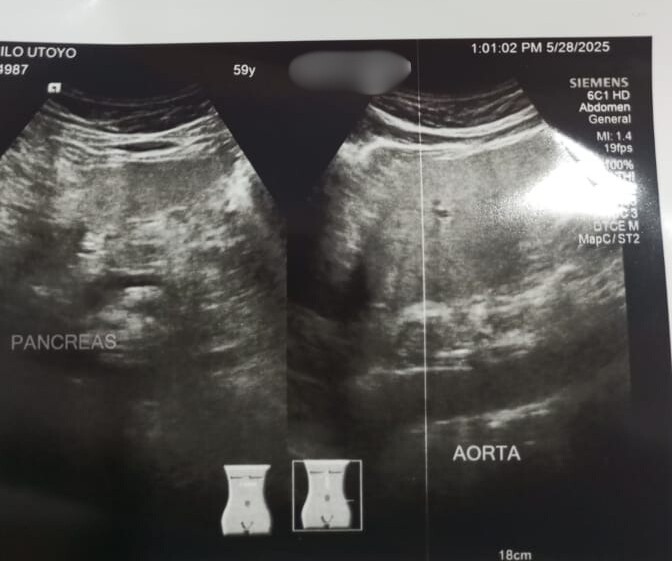

Awalnya saya sering merasakan nyeri di perut kanan atas yang menjalar ke pinggang kanan, terutama setelah duduk lama atau habis makan. Setelah diperiksa, diketahui ada batu empedu berukuran sekitar 7 mm.Setelah rutin mengonsumsi Lithozen selama kurang lebih 2 minggu, keluhan nyeri tersebut perlahan berkurang, perut terasa lebih nyaman, dan badan juga terasa lebih ringan. Saat ini aktivitas sehari-hari sudah jauh lebih enak dibanding sebelumnya